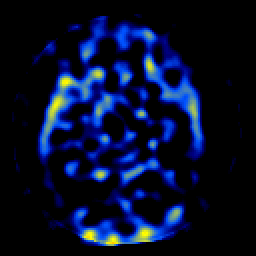

SPECT TL Study #7 -- Slice #25